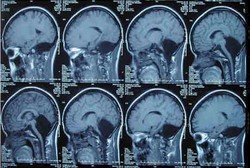

Sakit kepala sebelah atau migrain kerap dikaikta dengan penyakit insomnia hingga stres. Tak hanya itu, studi terbaru bahkan menemukan kaitan antara frekuensi migrain pada orang paruh baya dengan kemungkinan mengidap Parkinson.